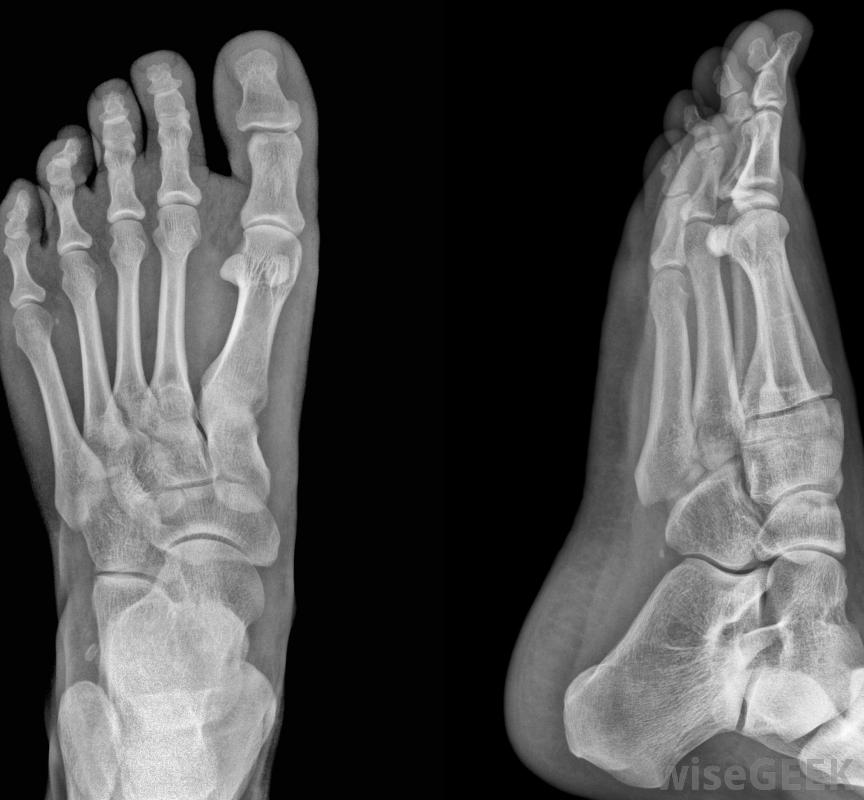

什么是腓骨籽骨(Fibular Sesamoid)?

腓骨籽骨是沿著足部第一個跖趾關節的下側發現的兩個小骨頭中的一個,這個關節位于大腳趾的底部。它和脛骨的籽骨一起,嵌在穿過關節的肌腱纖維中,也就是拇趾短屈肌(FHB)肌腱。這樣,這些骨頭支撐著FHB肌腱和拇趾長屈肌(FHL)的肌腱,在關節上起滑輪的作用,使大腳趾向下彎曲或卷曲,遠離關節。脛骨和腓骨的籽骨具有雙重功能,通過增加力臂來提高肌腱移動關節的有效性,并保護肌腱免受損傷在步態運動中,由于腳離開地面而產生的力。當腳離開地面時,籽骨會影響腳的力學性能形成第一跖趾關節的是第一跖骨,足部的長骨,在大腳趾的底部和足弓之間,以及第一近端指骨,大腳趾的近端骨。這是一個髁狀突或橢圓形關節,也就是說,跖骨遠端或遠端的凸面與指骨近端或近端的凹面相吻合,雖然腳趾在關節內可以左右移動,它的主要運動是屈伸運動:向下卷曲,向上抬起,屈伸運動是由拇短屈肌和長肌腱發起的,它們從足部和小腿相應的肌肉一直延伸到大腳趾的籽骨和指骨拇短屈肌本身分為兩個部分,通過兩條肌腱連接到近端指骨的底部,腓骨籽骨和脛骨籽骨都是在足底或腳底,籽骨是光滑的、圓的骨頭,腓骨籽骨靠近第二足趾,FHB肌腱的每一部分都在這些小骨的周圍運行,連接在近節指骨的底部。在兩個籽骨之間的間隙有一個凹槽,穿過該溝槽,在附著到遠端或遠處之前,穿過長屈肌肌腱,指骨。另外,拇內收肌肌腱的一部分,它將大腳趾向內拉向第二個腳趾,腓骨籽骨上的嵌件。當從地面上推出時,籽骨對腳的力學性能有影響。當腳趾向下彎曲時,它們可以防止FHB和FHL肌腱被跖趾關節擠壓在推開過程中,它們為FHL肌腱提供保護,它位于籽骨之間的溝壑中,而不是被跖骨和指骨壓在地面上。這些骨頭還充當跖趾關節的支點,增加足趾屈伸的力臂。力臂是指關節中心與通過關節的肌肉或肌腱之間的距離,也就是所謂的"力線"。換句話說,脛骨和腓骨的存在使FHB肌腱遠離其穿過的骨骼當肌肉收縮時,這種增加的力矩臂提高了拇短屈肌在繞關節旋轉大腳趾時的機械效率,與推離鉸鏈最遠的門的一側而不是靠近鉸鏈的一側推開門更有效。